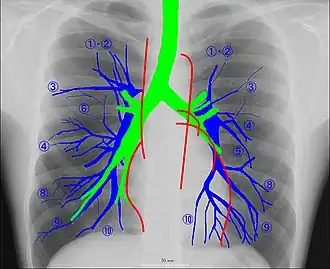

Рентгеноанатомия органов грудной клетки.

Рентгеноанатомия органов грудной клетки. Зелёным обозначены трахея и крупные бронхи, синим — ветви лёгочных артерий, красным — дуги тени сердца, цифрами отмечены сегменты лёгких.

При изучении рентгеноанатомии органов грудной клетки обращают внимание на рентгеновскую структуру видимых костей и мягких тканей грудной клетки; форму и прозрачность для рентгеновских лучей областей, на которые проецируется лёгочная ткань (так называемых «лёгочных полей»), а также их структуру, сформированную тенями сосудов лёгких («лёгочный рисунок»); расположение и структурность корней лёгких; положение, форму куполов диафрагмы и синусов плевральных полостей; форму и размеры тени средостения (в том числе сердца).

Лёгкие на рентгенограмме образуют лёгочные поля, располагающиеся по обе стороны от интенсивной тени средостения. Правое лёгочное поле короче и шире левого. В лёгочных полях различают верхушки (зоны выше ключиц), верхние отделы — от верхушек до передних отрезков вторых рёбер, средние отделы — между вторыми и четвёртыми парами рёбер, и нижние отделы — от четвёртых рёбер до диафрагмы. Лёгочные поля в норме очень светлые (тёмные на негативе) из-за высокой рентгенопроницаемости заполненной воздухом лёгочной ткани. Структура лёгочных полей называется лёгочным рисунком, анатомическим субстратом которого являются лёгочные сосуды и, в малой степени, лёгочный интерстиций. Лёгочный рисунок визуализируется в виде переплетения сосудистых теней тяжистого, округлого и овального вида, более интенсивных в местах их пересечений. В направлении от корней лёгких к периферии рисунок лёгочных сосудов становится беднее и совсем не визуализируется на расстоянии 1—1,5 см от края лёгочных полей. Лёгочный рисунок наиболее густой в нижних отделах лёгочных полей, обедняясь к верхушкам. Тени бронхов на рентгенограмме визуализируется в виде двойных полосок или колец с просветлением внутри.[3][4]

Тень корней лёгких определяется парамедиастинально на уровне передних отрезков II—IV рёбер, левый корень располагается несколько выше правого и частично скрыт тенью средостения. Ведущим анатомическим субстратом в формировании тени корней лёгких являются лёгочные артерии и бронхи, в меньшей степени — лёгочные вены и другие структуры. В норме корни лёгких имеют неоднородное изображение, представляя собой структурированную совокупность элементов различной плотности. В корнях лёгких различают головку, тело и хвост. Правый корень визуализируется на всём протяжении в виде лентовидной, суживающейся книзу изогнутой тени средней интенсивности, отделённой от тени сердца промежуточным и нижнедолевым бронхами. К периферии от корней лёгких отходят лёгочные сосуды, причём артериальные ветви имеют более вертикальное направление, венозные — более горизонтальное. Ширина корня лёгкого соответствует ширине его основного артериального ствола; в норме она равна ширине бронха, отделяющего корень от средостения, и не превышает 1,5 см.[3][4]

Сердечно-сосудистая тень занимает центральное положение на рентгенограмме органов грудной клетки. На рентгенограмме в прямой проекции её контуры в норме формируют две дуги справа и четыре — слева. Нижняя дуга правого контура образована правым предсердием, верхняя, более медиальная — восходящей частью аорты и верхней полой веной. Первая (верхняя) левая дуга образована дугой и начальным отделом нисходящей аорты, вторая — лёгочным стволом, третья — ушком левого предсердия, четвёртая — левым желудочком. В области второй и третьей дуг контур тени средостения вогнут и носит на этом уровне название «талия сердца»; эта зона является границей между сердцем и связанными с ним сосудами.[5]